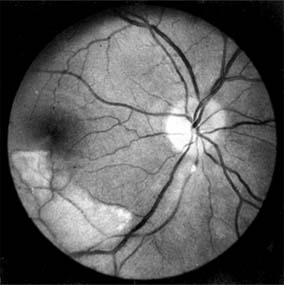

The appearance of the fundus in hypertensive retinopathy is determined by the degree of elevation of the blood pressure and the state of the retinal arterioles. Thus, in young patients with accelerated hypertension, an extensive retinopathy is seen, with hemorrhages, retinal infarcts (cotton-wool spots), choroidal infarcts (Elschnig's spots), and occasionally serous detachment of the retina (Figure 15-10). Severe disk edema is a prominent feature. Vision may be impaired but is restored if blood pressure is reduced with caution.

Figure 15-10

Figure 15-10: Accelerated hypertension. Fluorescein angiogram in a young man showing arteriolar constriction, dilation of capillaries with microaneurysms, and areas of closure. Marked disk edema is present.

In contrast, elderly patients with arteriosclerotic vessels are unable to respond in this manner, and their vessels are thus protected by the arteriosclerosis. It is for this reason that elderly patients seldom exhibit florid hypertensive retinopathy (Figure 15-11).

Figure 15-11

Figure 15-11: Accelerated hypertension. Fluorescein angiogram in an elderly wom.an showing marked arteriolar constriction and irregularity but few signs of florid retinopathy.